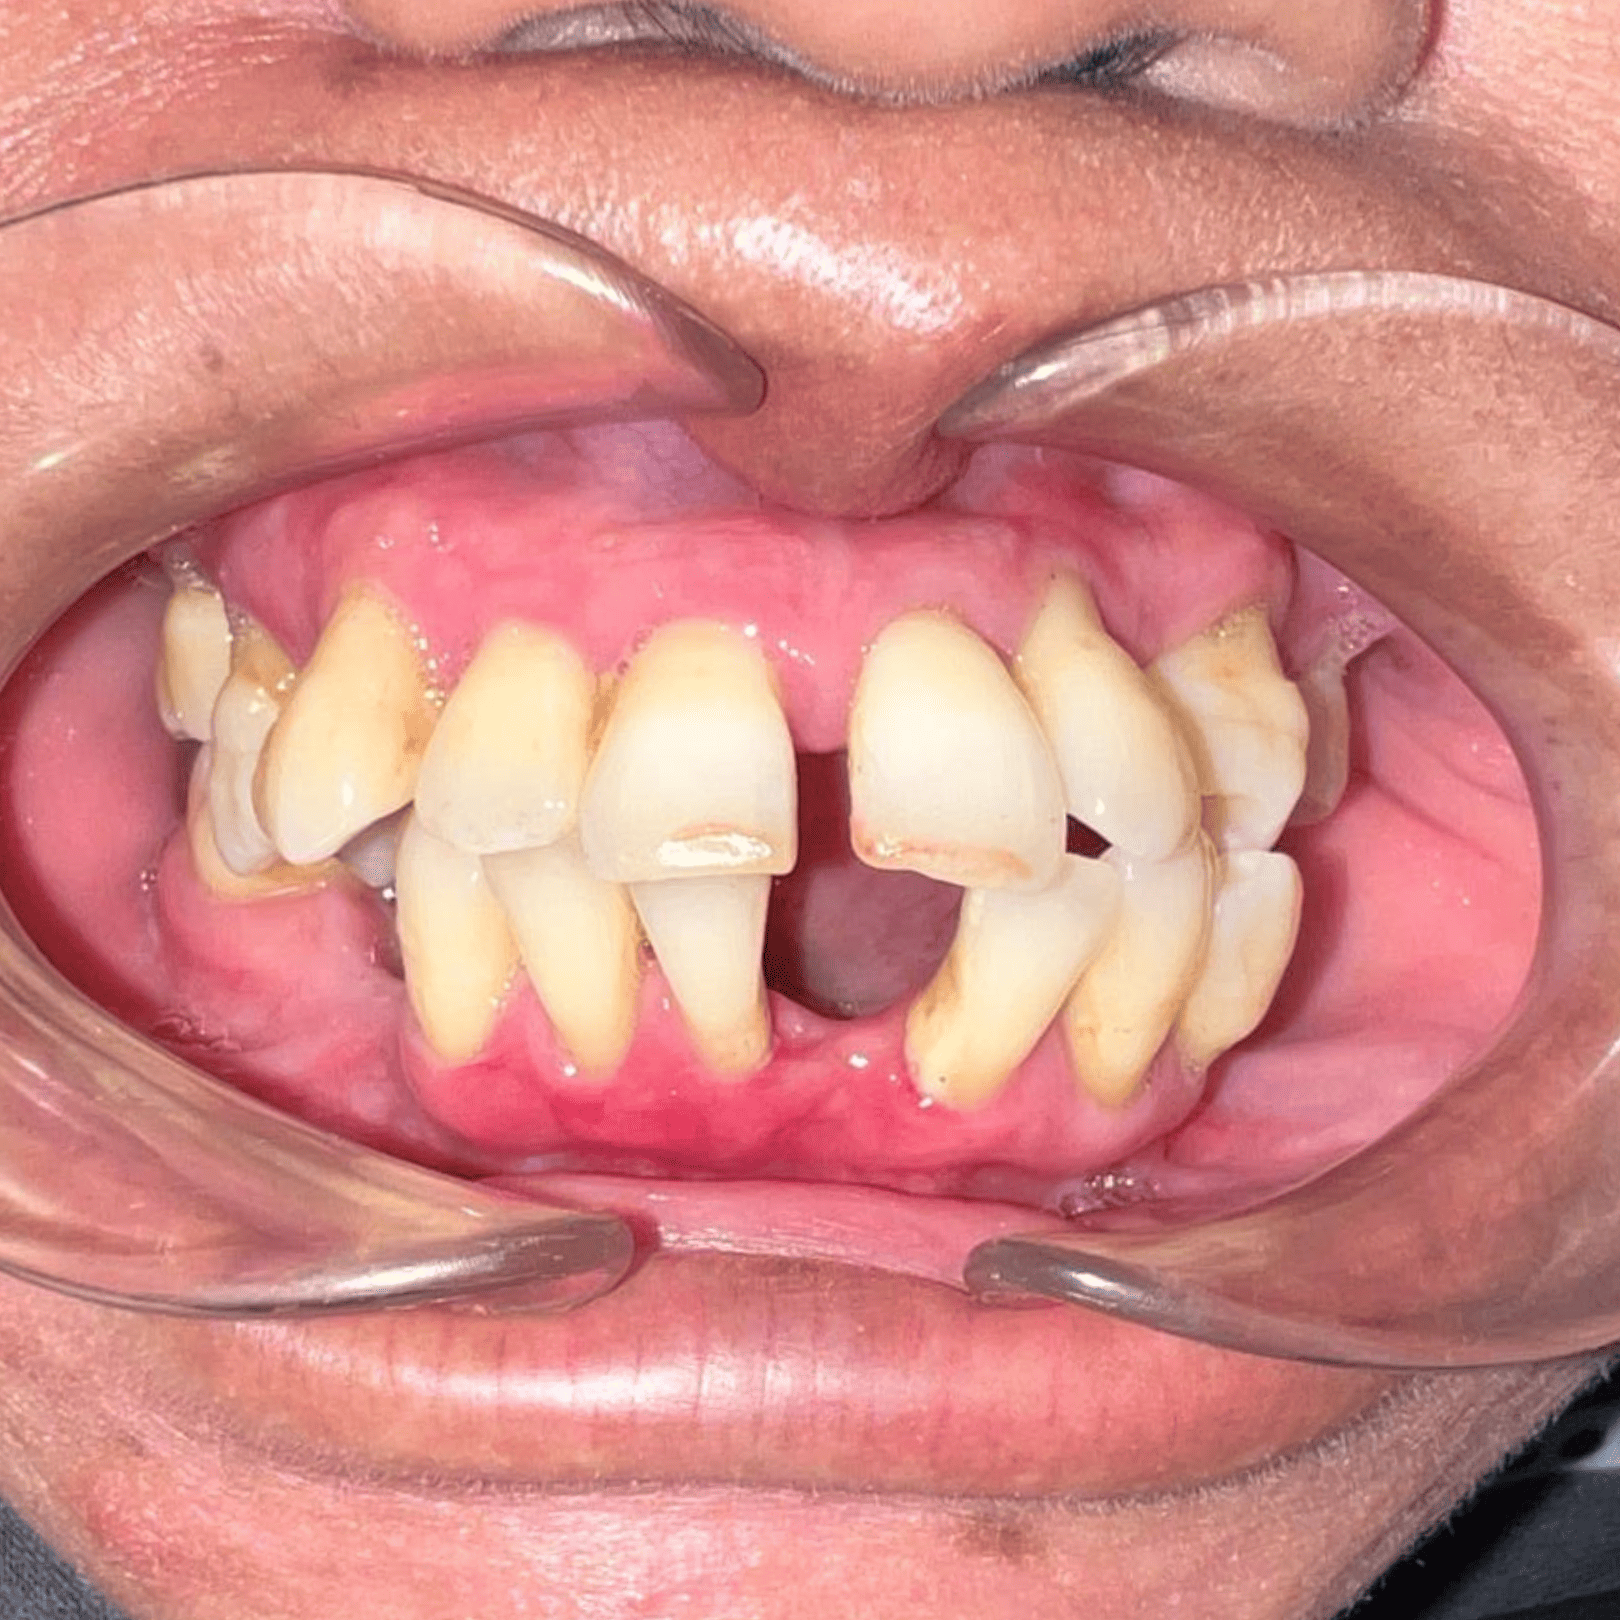

Before & After

📸 Before: Edentulous (no teeth) upper/lower jaw

📸 After: Full set of teeth fixed securely with All-on-4 implants